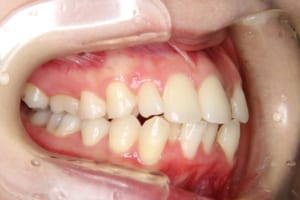

埋伏していた上顎犬歯によって上の前歯の歯根が吸収を伴っていたケースの治療例

年齢・性別 19才 女性

治療期間 4年6か月

費用(保定除く) 889,550円(税込)